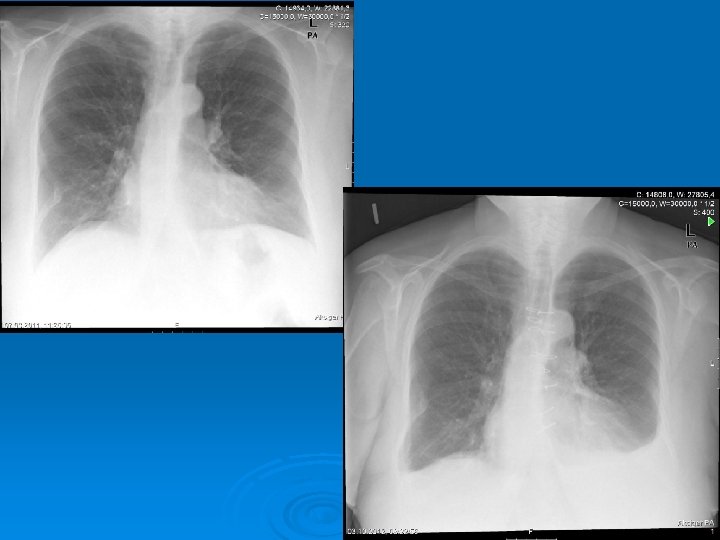

Radiology The fluid initially accumulates in the more dependent recesses of the thoracic cavity forming a Damoiseau Line Ø 200 -300 ml of pleural effusion can be detected on standard chest radiograph as blunting of the costophrenic angle Ø

Ø Massive pleural fluid often shifts the mediastinum to the opposite side Ø Unusual localized pleural effusions can be seen due to the localized obliteration of the pleural space often by inflammatory conditions (adherence)

Ø Smaller amounts of pleural fluid can be detected on lateral decubitus radiography as the free intrapleural fluid moves from top of the diaphragm to the dependent chest wall Pleural effusion in a lateral decubitus radiograph